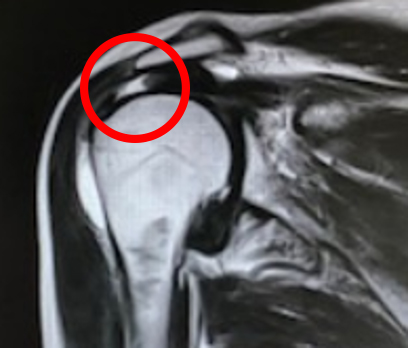

通常のレントゲン画像では分からないことが多く、腱板が描出可能なMRIや超音波の画像検査により診断できます【図2】。

【図2】MRI画像

断裂部の輝度上昇(白く見える)が確認できます。